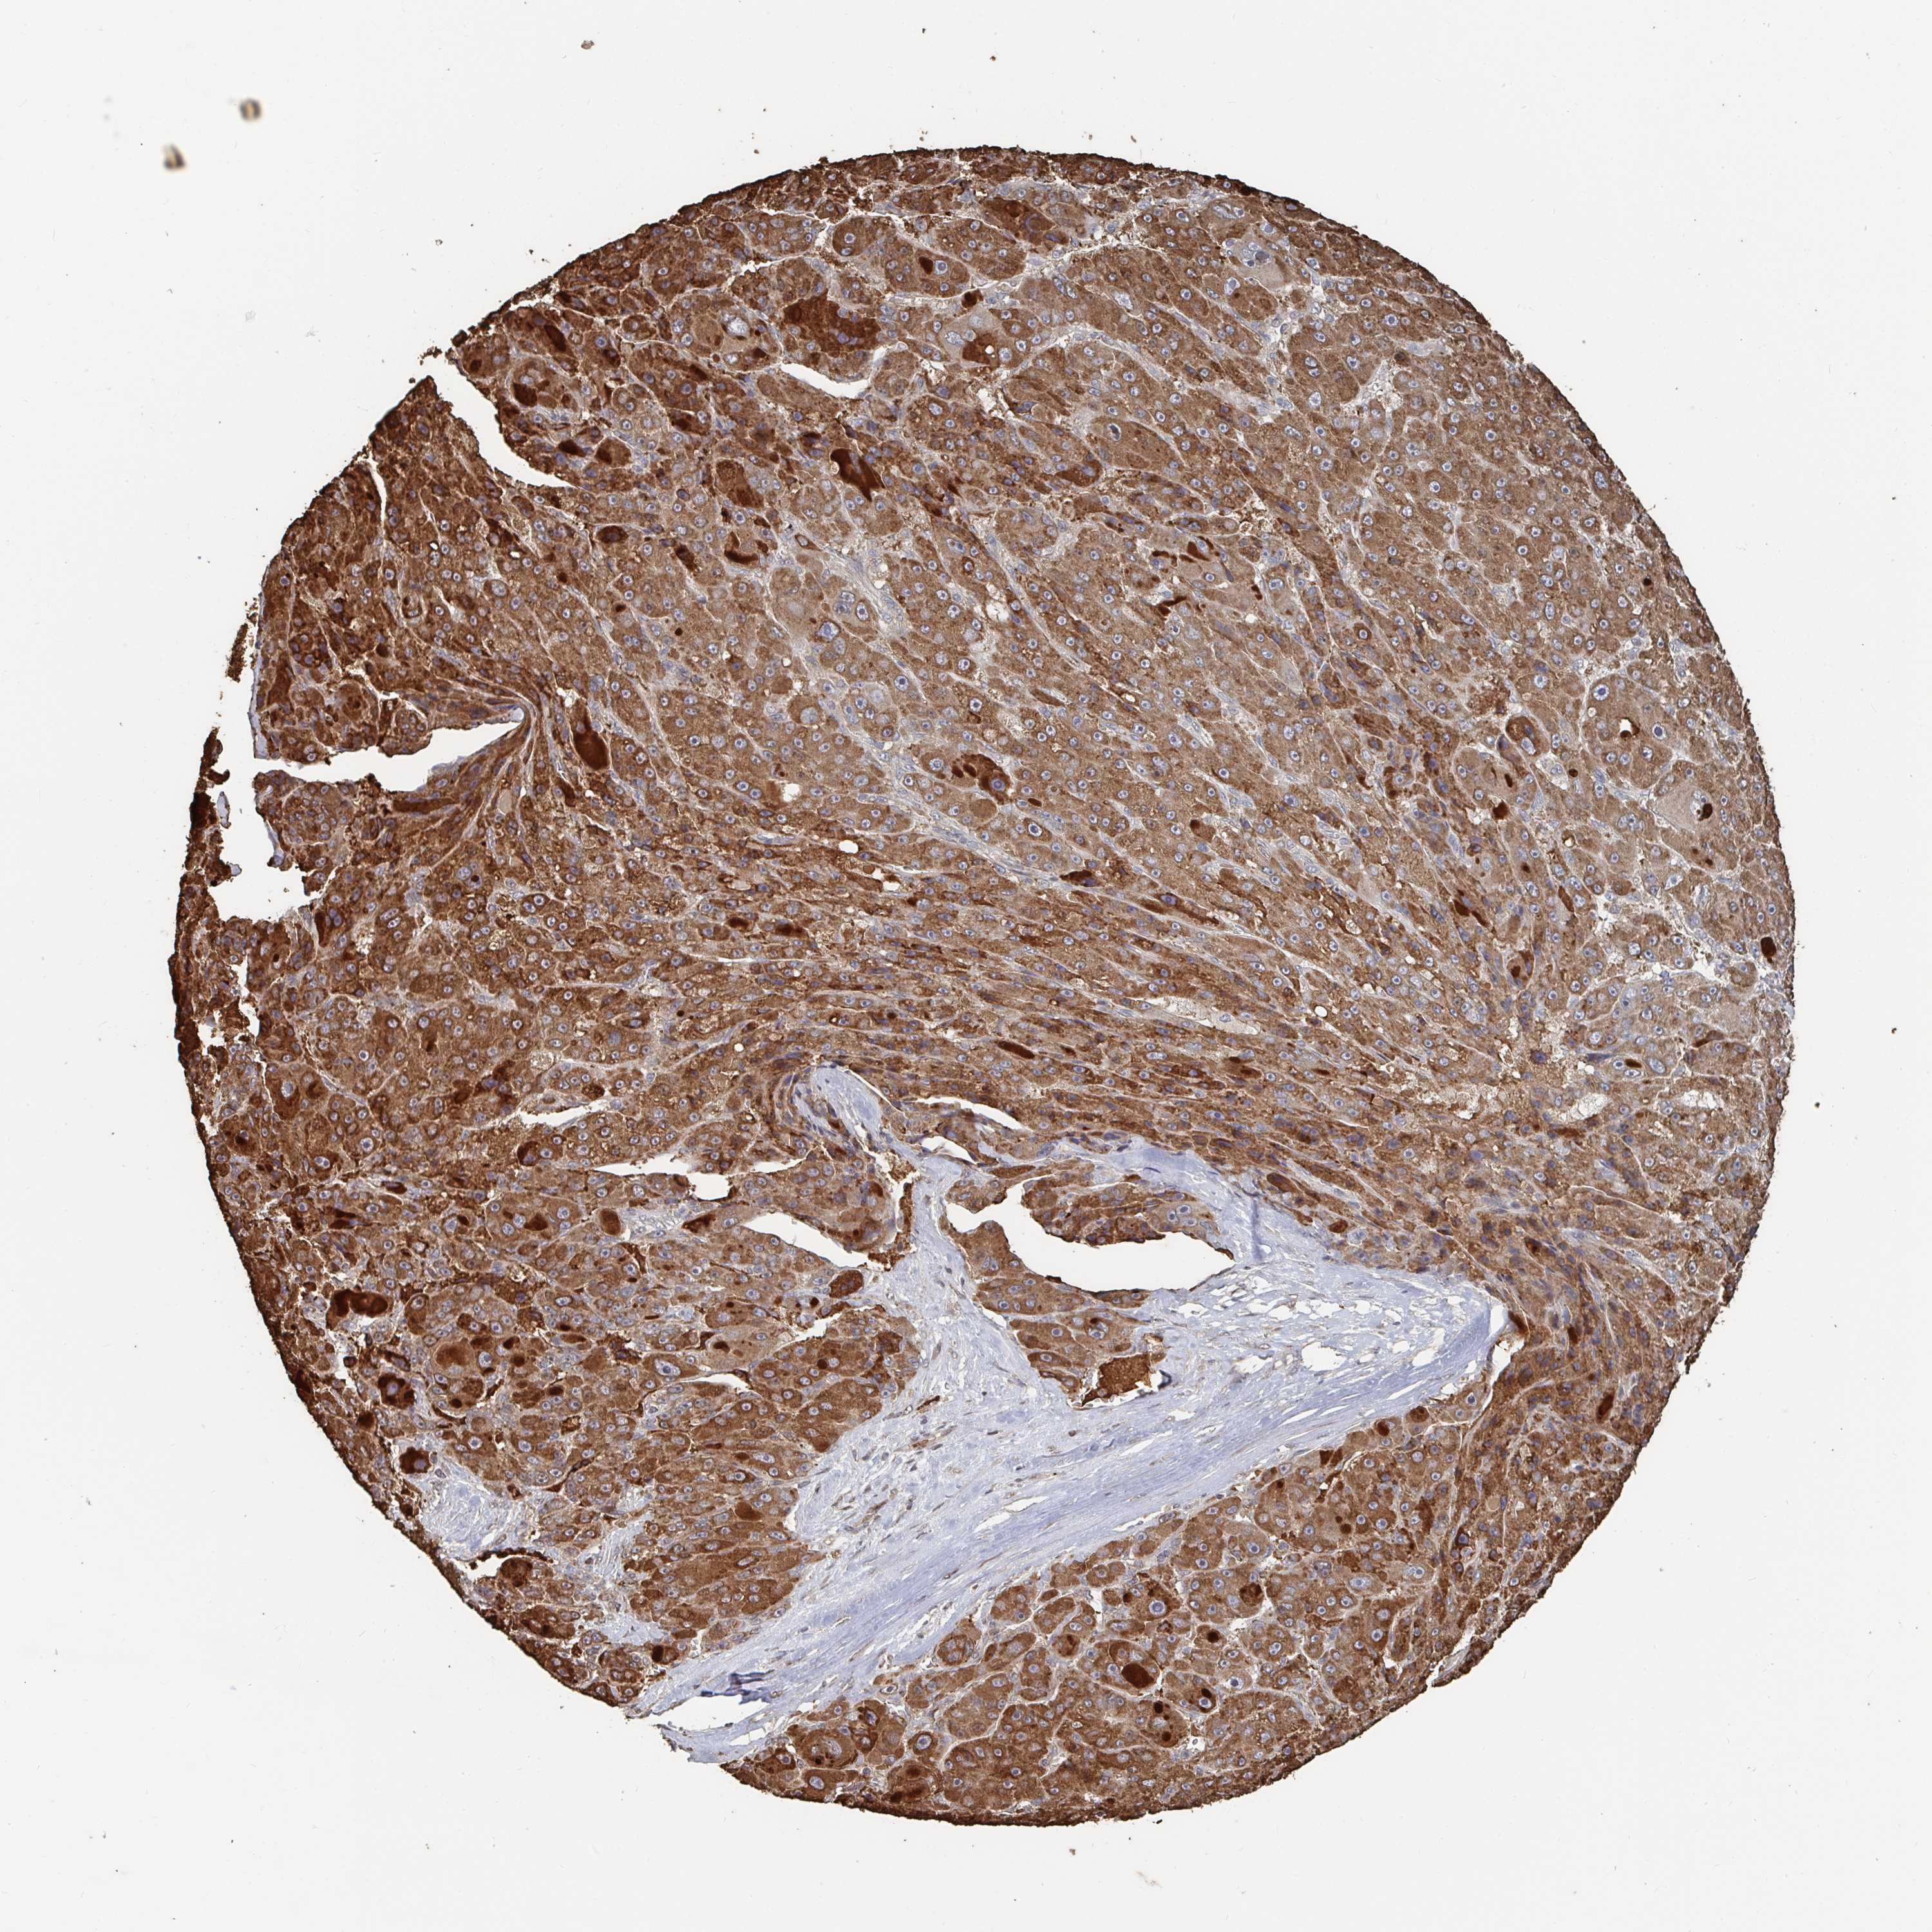

LIVER CANCER - Protein expressioni

A mouse-over function shows sample information and annotation data. Click on an image to view it in a full screen mode. Samples can be filtered based on level of antibody staining by selecting one or several of the following categories: high, medium, low and not detected. The assay and annotation is described here.

Note that samples used for immunohistochemistry by the Human Protein Atlas do not correspond to samples in the TCGA dataset.

Antibody stainingi

Antibody staining in the annotated cell types in the current human tissue is reported as not detected, low, medium, or high, based on conventional immunohistochemistry profiling in selected tissues. This score is based on the combination of the staining intensity and fraction of stained cells.

Each image is clickable and will lead to virtual microscopy that enables deeper exploration of all samples and also displays staining intensity scores, fraction scores and subcellular localization as well as patient and tissue information for each sample.

Antibody HPA061939

Staining

High

Medium

Low

Not detected

Intensity

Strong

Moderate

Weak

Negative

Quantity

>75%

75%-25%

<25%

None

Location

Nuclear

Cytoplasmic/membranous

Cytoplasmic/membranous,nuclear

Cholangiocarcinoma

Carcinoma, Hepatocellular, NOS